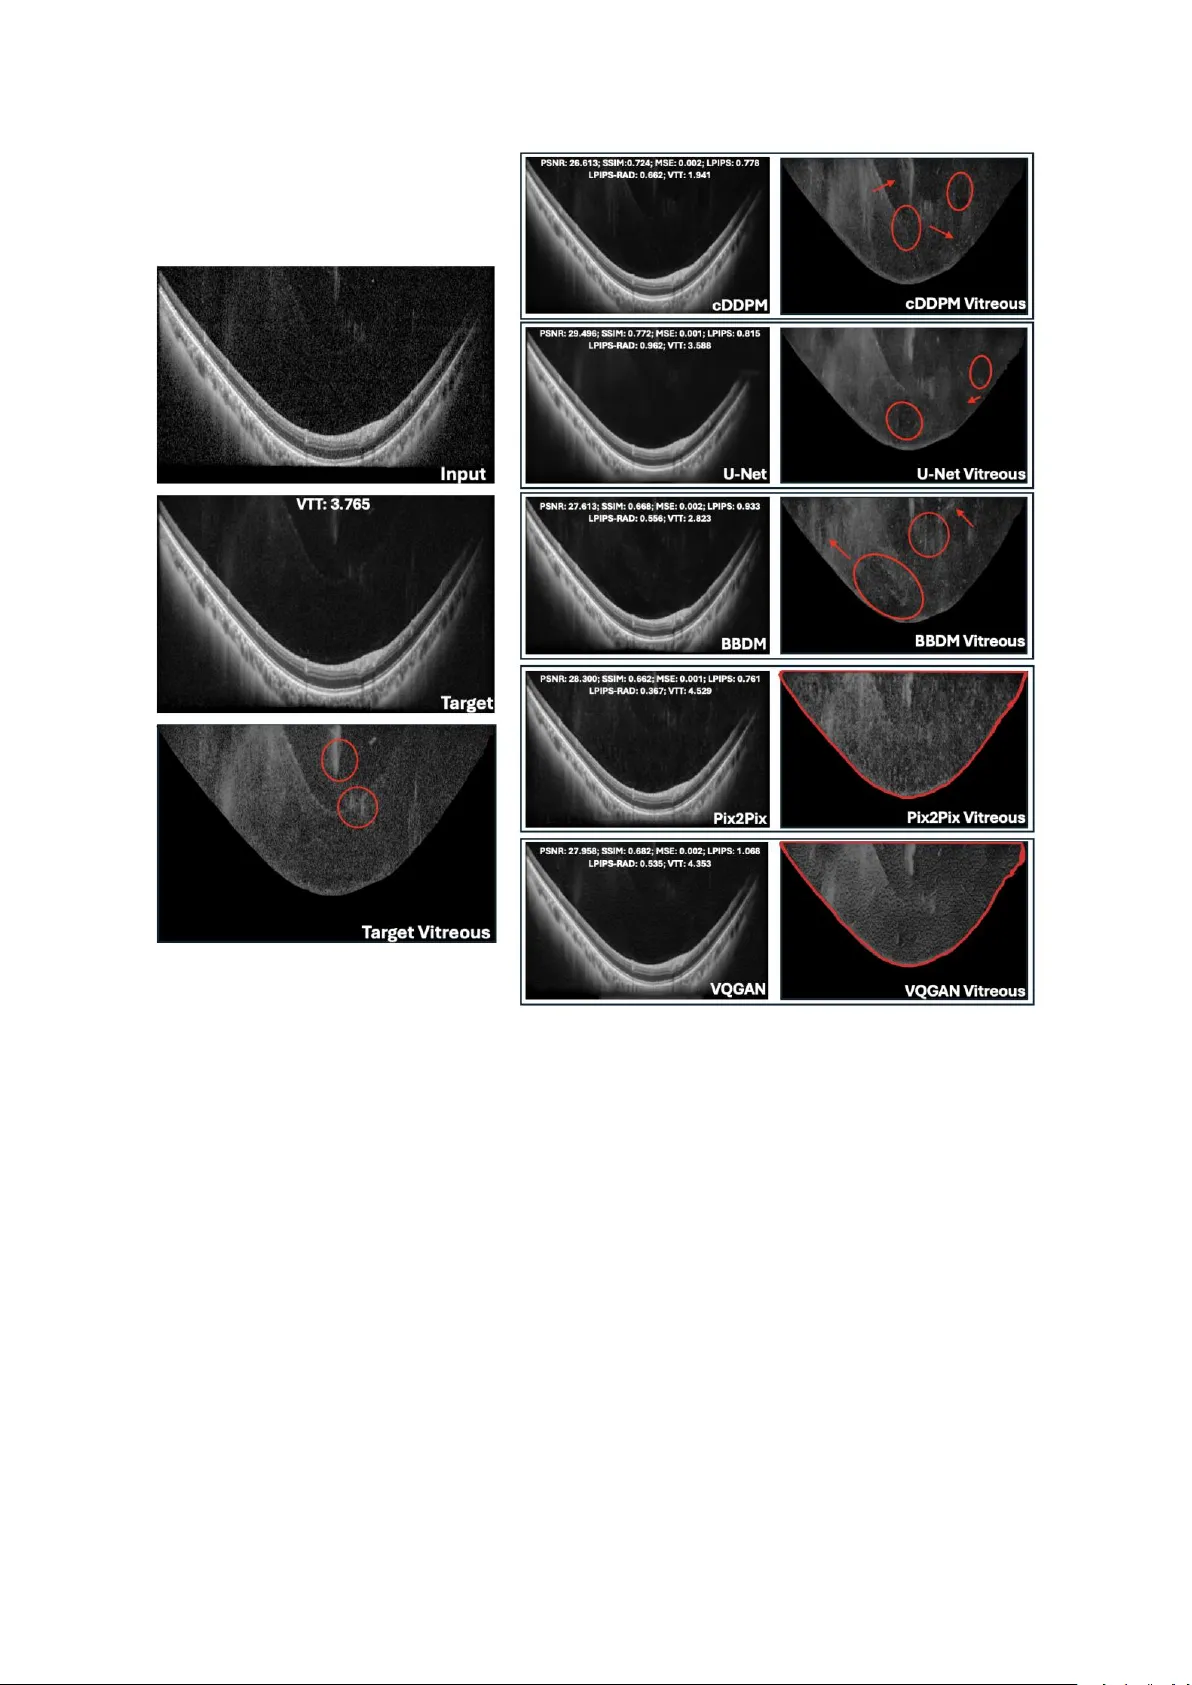

본 연구는 조건부 디노이징 확산 확률 모델(cDDPM) 등 다섯 가지 딥러닝 기법을 이용해 저품질 SD‑ART10 유리체 OCT 영상을 고품질 SD‑ART100 영상으로 변환한다. 정량적 지표와 안과 전문의의 시각적 평가를 모두 적용했으며, cDDPM이 임상적 해부학적 충실도와 이미지 왜곡 최소화 측면에서 가장 우수함을 확인했다.

정량 평가는 PSNR, SSIM, LPIPS 세 가지 지표를 사용했으며, 각각 신호‑대‑노이즈 비, 구조적 유사도, 그리고 인간 시각에 근접한 인지적 차이를 측정한다. U‑Net이 PSNR 30.23 dB와 SSIM 0.820으로 최고 성능을 보였지만, LPIPS에서는 Pix2Pix(0.697)와 cDDPM(0.753)이 더 낮은 값을 기록해 인간이 느끼는 시각적 차이는 낮았다. 이는 전통적인 픽셀‑레벨 손실 최소화가 구조적 유사도는 높이지만, 실제 임상적 해석에 필요한 미세 조직 특징을 충분히 복원하지 못할 수 있음을 시사한다.

시각적 튜링 테스트는 두 단계로 진행되었다. 첫 번째에서는 5개 모델을 모두 제시하고 안과 전문의가 ‘가장 실제와 가까운’ 이미지를 순위 매겼으며, cDDPM이 평균 3.07점으로 최고 점수를 받았다. 두 번째 테스트에서는 최고 모델만을 대상으로 ‘가짜와 진짜를 구분 못할 확률(속임수율)’과 ‘해부학적 보존율’을 평가했는데, cDDPM은 32.9%의 속임수율과 85.7%의 해부학적 보존율을 기록했다. 이는 정량 지표와는 별개로, 임상 의사가 실제 진단에 활용할 수 있는 수준의 이미지 품질을 제공한다는 강력한 증거다.

추가 실험에서는 새로 획득한 데이터에 대해 cDDPM을 적용했을 때, ART1(단일 획득)이나 ART10(10배 평균)보다 전체 이미지 PSNR이 높았으며, 특히 유리체 영역만을 별도로 세분화한 경우 ART100 기준에 가장 근접한 PSNR을 달성했다. 이는 모델이 저해상도 입력에서도 핵심 구조를 효과적으로 복원한다는 것을 의미한다.